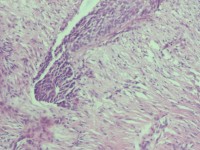

宫颈活检组织

性别

女

年龄

43岁

临床诊断

宫颈病变

一般病史

宫颈癌筛查:hpv16(+))

标本名称

宫颈组织

大体所见

灰白色组织

老师们看看,高级别累腺吗